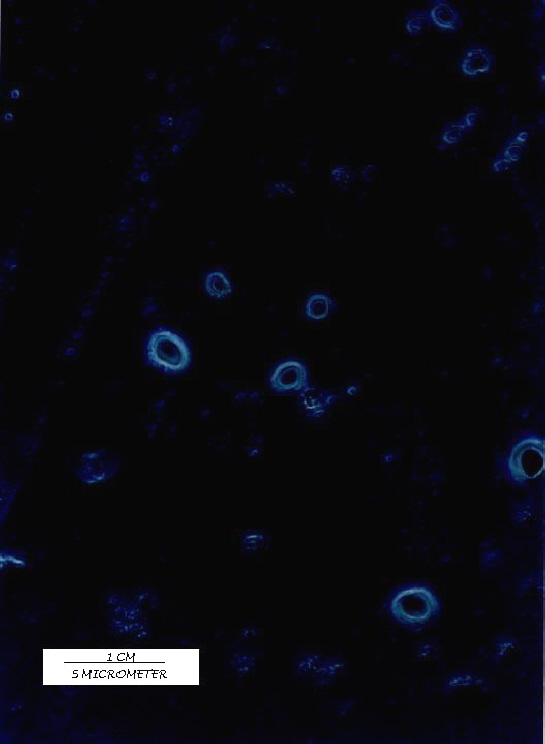

Photomicrography

All the batches of the liposomes prepared were observed under Olympus (BX 40F4, Tokyo, Japan) microscope with a polarizing attachment to study their size and lamellarity. A Photomicrograph under 1000x magnification is shown in figure 1.

Figure 1: Acyclovir liposomes prepared by REV method.

Twenty-seven batches of ACY liposomes were prepared by REV method by using 33 factorial design (table 1) varying three independent variables volume of organic phase (x1), volume of aqueous phase (x2) & Drug/PC/CHOL in molar ratio (x3). The PDE (dependent variable) of prepared batches was determined and the results are recorded in table 2. Prepared liposomes were also observed under 1000x magnification using Olympus (BX 40 F4, Japan) microscope to examine their size and lamellarity. The liposomes were found to be oligolamellar with large aqueous core. The mean geometric diameter of oligolamellar type vesicles varies from 3.2 to 5.0 mm with geometric standard deviation (sg ) from 1.5 to 2.3 as shown in table 2. A substantial high drug entrapment achieved in liposomes prepared by REV method was 71.1% at -1 level of x3 (1:2:0.5), 0 level of x1 (6 ml) and -1 level of x2 (1 ml).